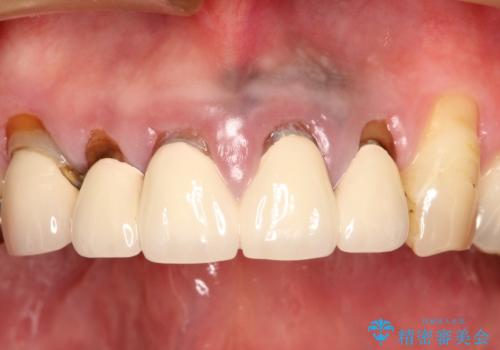

- 上の前歯の根元が黒くなっているので、再治療をしたいとのことで来院された患者様です。

レントゲンを撮影すると、適合不良のかぶせ物が装着されており、根の治療も不十分であることが確認されました。

適合不良のかぶせ物をすべて除去して、根の中の治療から再治療を行うこととなりました。

適合不良のかぶせ物が装着されていた歯は、内部がやはり虫歯になっていました。